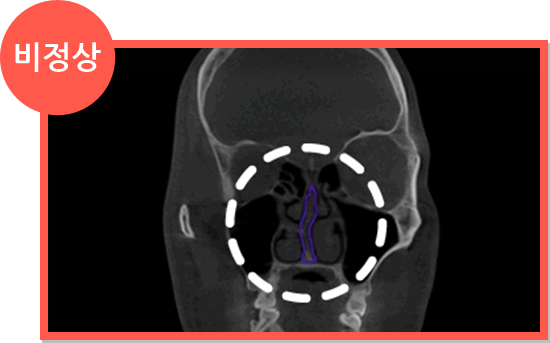

CT

CT

A.구조 이상에 의한 비염

- 비중격만곡증에 의한 비염

- 비중격 연골이 휘어서 생긴 비염은 휘어진 비중격 연골을 교정하면서 비염 수술을 같이 해야 합니다.

세계적으로 인정받는

Amorphous Silicon Flat Panel

센서를 사용하여 선명한 고화질로

환자의 상태를 볼 수 있어

정확한 진단이 가능한 CT로 진단

세계적으로 인정받는

Amorphous Silicon Flat Panel

센서를 사용하여 선명한 고화질로

환자의 상태를 볼 수 있어

정확한 진단이 가능한 CT로 진단